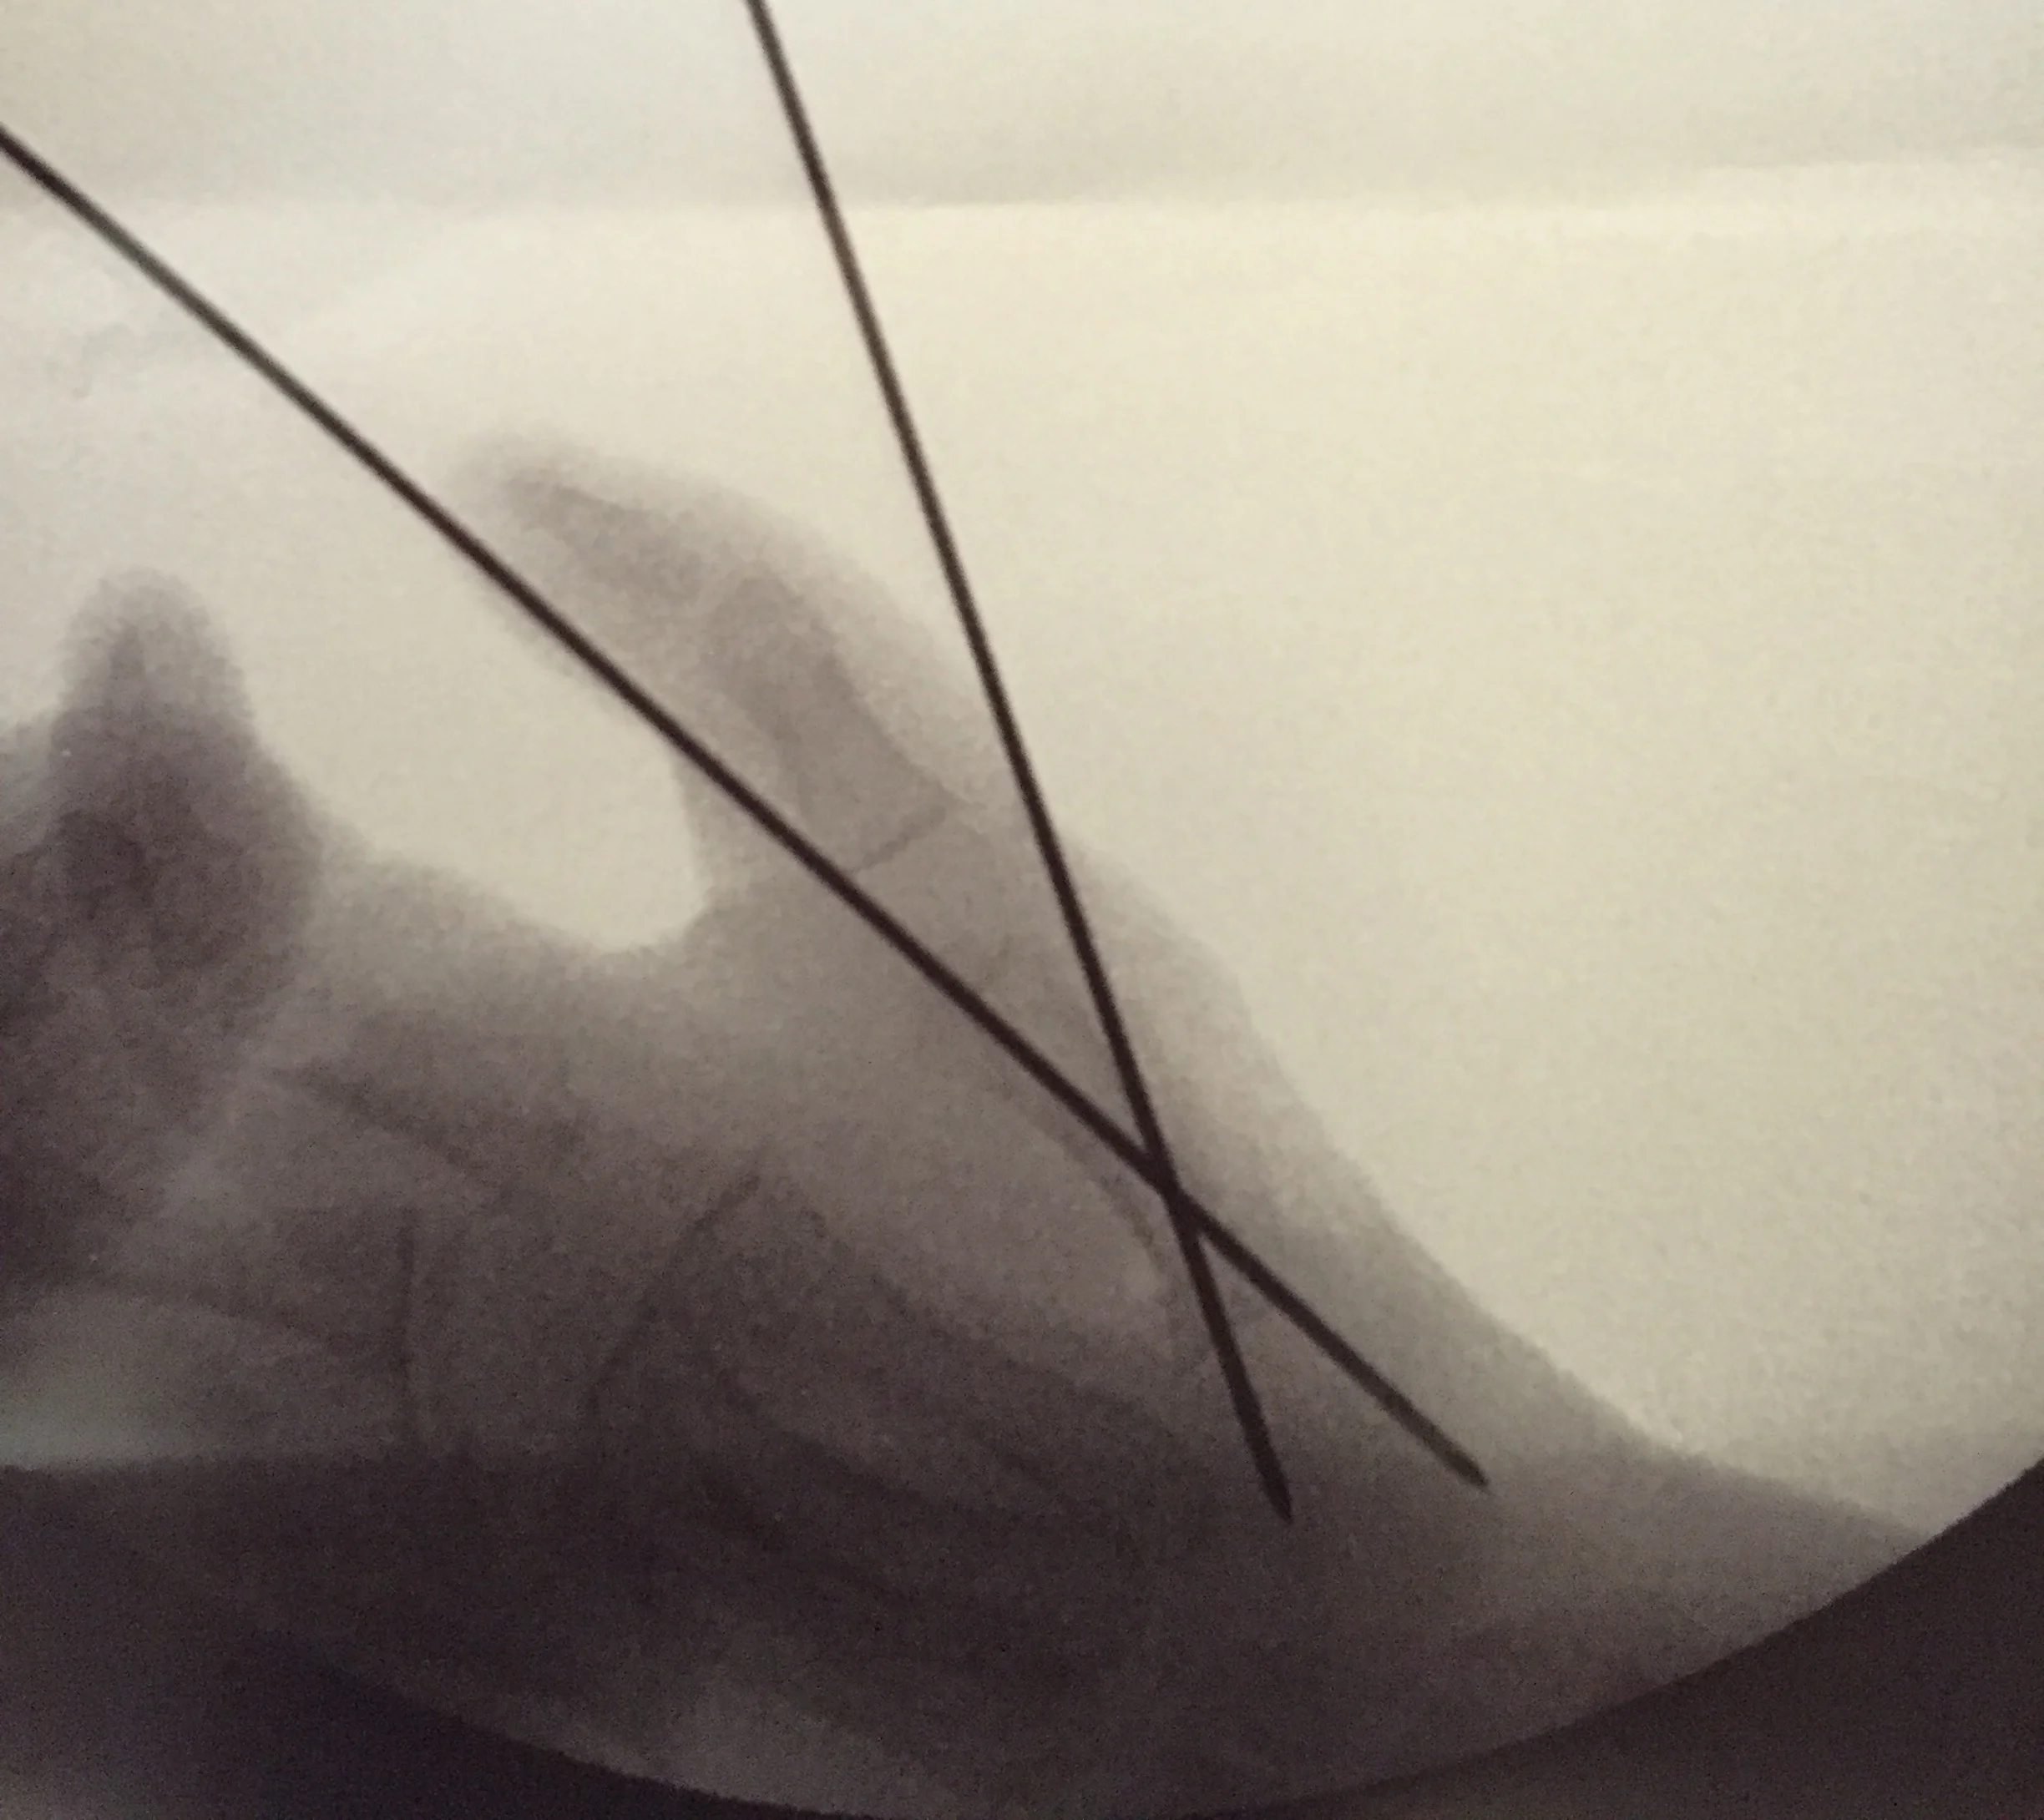

Hand surgery is behind us. Probably by the time I finish writing and uploading this post, the first three days post surgery will be also be behind us. Three days is the length of time I hear hand surgery pain is the most intense. Managing Nathaniel’s pain has been tricky and some unexpected respiratory issues complicated our post surgery hospital stay. But today I catch myself taking deep breaths and releasing loud exhales of relief. The big day is over. The surgeon cut Nathaniel’s right thumb metacarpal, rotated it to one hundred and ten degrees, and pinned it back together. The doctor then sliced a segment of muscle on the pinky side of Nathaniel’s hand and brought it over to support the thumb and increase thumb to finger opposition. Wow. The whole thing amazes me. We will know the final outcome of the surgery in five weeks when Nathaniel’s cast comes off. But for now we rest in the surgeon’s explanation that things went well. I am glad the last four days are behind us.